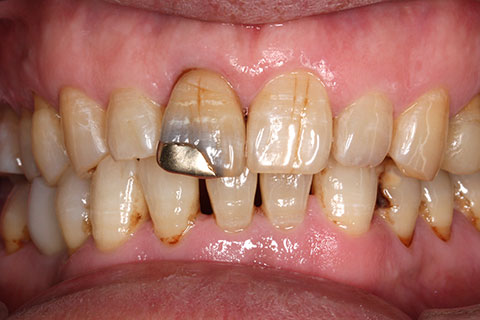

• オールセラミックの症例6

治療前

治療後

40年前の金歯をジルコニアセラミックスで治療。

年齢・性別

65歳男性

治療期間

1ヶ月

抜歯

なし

治療費

8.8万円

備考

金歯をセラミックス冠に変更。

治療内容

歯質を削除し、セラミック冠をセメント合着

施術の副作用(リスク)

知覚過敏、歯髄炎、荷重負担